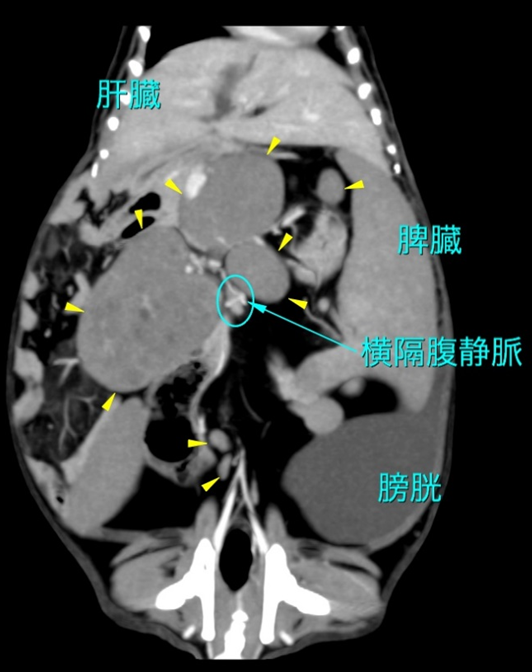

確定診断には、リンパ球の異常な増殖を証明するための組織サンプルの採取が不可欠です。 診断的ワークアップとして、血液検査(CBC、血液化学検査)を行い、全貌の確認のために X線検査(特に胸部、縦隔腫瘤や胸水の評価)および腹部超音波検査(腹腔内リンパ節、肝臓、脾臓、消化管の評価)が必須です 。超音波検査は、細胞診や生検のためのサンプル採取のガイドとしても極めて有用です 。さらなる詳細にはCTやMRIも有用です。

臨床病期分類(クリニカル・ステージング)

腫瘍の全身への広がりを定義するために、すべての症例でステージング(病期分類)を行う必要があります 。イヌやネコで用いられるWHO(世界保健機関)の5段階ステージングシステムが最も一般的に推奨されます 。

| ステージ III | 横隔膜の両側にある複数の(全身性)リンパ節の転移。 |

| ステージ IV | 肝臓および/または脾臓の浸潤(リンパ節の関与の有無を問わない) |

| ステージ V | 血液(白血病)または骨髄、および/または他の臓器(CNS、眼、腎臓など)への浸潤 |